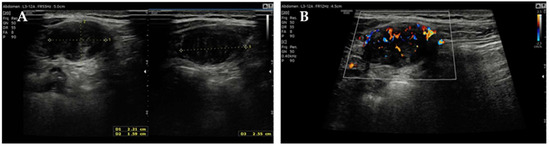

Elective excision was scheduled for August 2024 at our Clinic. Pre-operative blood tests, including complete blood count, hepatic and renal panels, and tumor markers, were within normal ranges, except for a mildly elevated α-fetoprotein level (8.5 ng/mL; reference < 5.8 ng/mL) while the patient was breastfeeding. Pre-operative US depicted an encapsulated, heterogeneous, moderately vascular mass measuring 86 mm (Figure 3) and suggested either endometriosis or splenosis.

Figure 3.

Pre-operative transabdominal US: (A) measurement of the lesion and (B) color-Doppler vascularization.